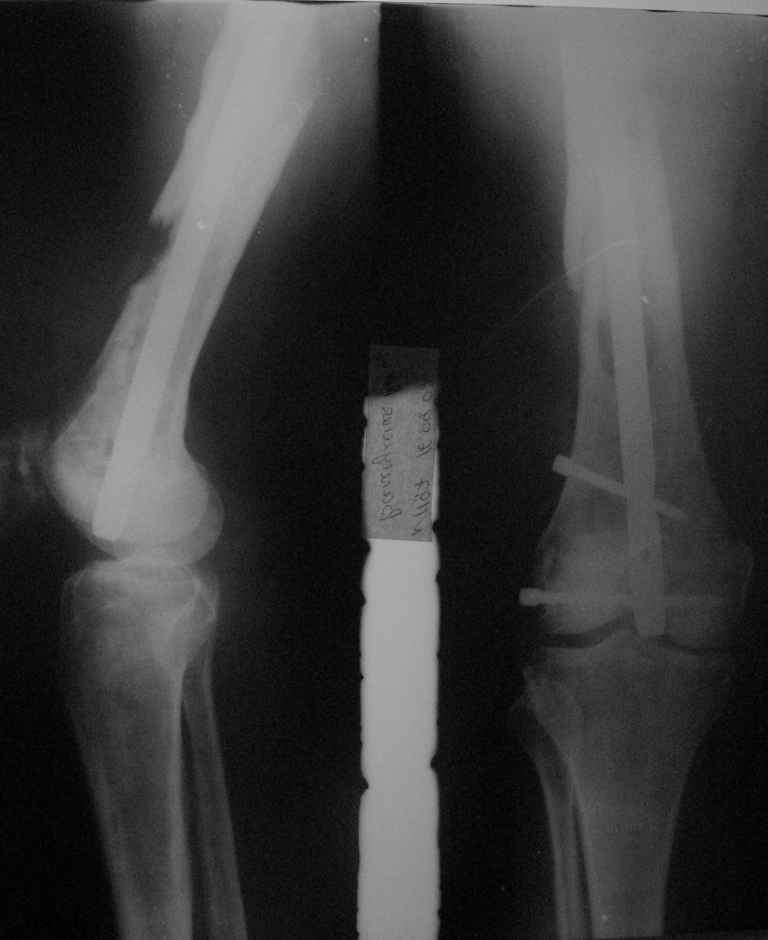

Приветствую, коллеги. 2 года назад пациентке поставлен диагноз саркома бедра,

1.5 года назад произведен синтез для улучшения качества жизни для по поводу патологического перелома на уровне открытой биопсии. Через 4 месяца открытый реостеосинтез с исправлением оси и восстановления опроспособности. В период после перелома лучевой и химиотерапии не получала. Месяц назад появилсь возрастающие боли в суставе. Ходит с тростью. Движения в коленном суставе качательные.На рентгеннограммах после реостеосинтеза намечалась тенденция к сращению. В области операционной раны периодически открывался-закрывался свищ. На последних - кроме миграции гвоздя в сустав - лизис костной мозоли. Можно ли одной из причин миграции считать длительную статическую фиксацию гвоздя? У кого-нибудь есть опыт на каких сроках проводить у онкобольных динамизацию? Что можно сделать для ликвидации боли и поддержания опороспособности конечности? Имеет ли смысл установка более толстого фиксатора без дистального блокирования? И вообще,ставить ли здесь вопрос о сохранении конечности?